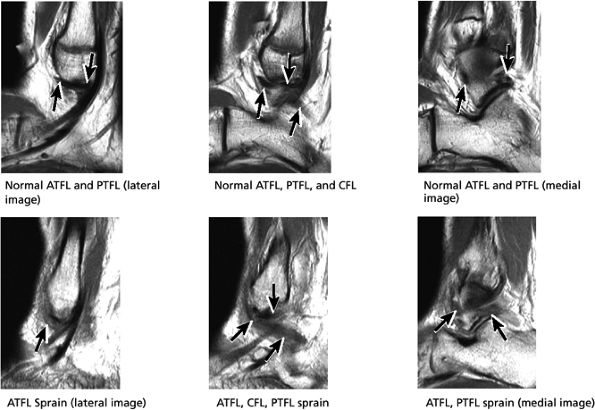

Lateral ligaments (the anterior talofibular, calcaneofibular, and posterior talofibular ligaments)

The ATFL is found on sagittal images one slice central to the lateral-most sagittal slice that includes the lateral malleolus. The origin of the ATFL is seen at the anterior inferior tip of the lateral malleolus. The anteromedial course of the ATFL can be followed on the next two images moving centrally, to where it inserts on the talus.

-

The posterior talofibular ligament (PTFL) is located in a similar fashion. The origin of the PTFL is at the inferior tip of the lateral malleolus, and the tendon can be followed medially to its insertion on the mid-posterior aspect of the talus. The PTFL is seen in cross-section on sagittal images and has a cord-like appearance. Posterior to the talus, this cord-like appearance should not be mistaken for a loose body in the posterior joint.

this image (or possibly one image posterior). On the next one or two posterior images the course of the CFL can be followed from the distal lateral malleolus posteroinferiorly to its insertion on the lateral calcaneus. On the three or four images anterior to the slice through the middle of the lateral malleolus, the full course of the ATFL is seen as a dark bundle of fibers moving directly anteriorly to insert on the lateral aspect of the talus. The lateral ligaments are examined in the coronal plane, and any findings are correlated with those seen in other planes.